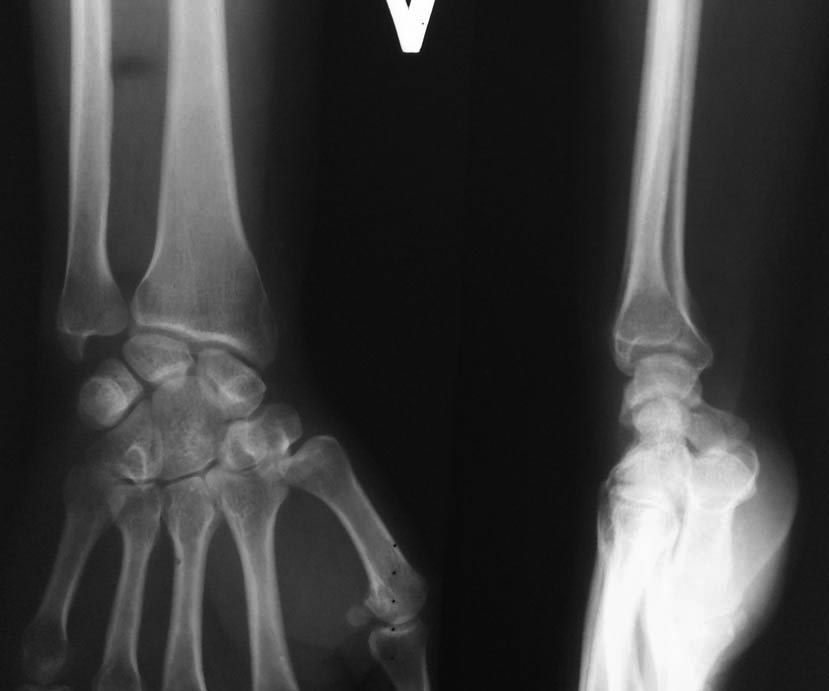

Rg-здоровой руки

По простым снимкам (а по КТ еще лучше) видно, что суставная поверхность отклонена к тылу, кисть на подвывихе, есть внутрисуставная деформация. Укорочение локтевой кости только усилило проблемы, а тут еще и несращение...

В имеющейся ситуации мы наверное выполняли бы корригирующую остеотомию дистального отдела луча с восстановлением хотя бы ладонной инклинации (вопрос об устранении внутрисуставной деформации наверное уже решен ввиду большого срока после травмы). И да, придется ее тоже укорачивать уже подстраиваясь под локтевую.

Случай сложный и наверняка здесь действует несколько механизмов формирования боли. Это и ложный сустав локтевой кости, и тыльный подвывих кисти (хорошо виден на срезе КТ, обозначенном стрелкой), и нарушения в лучелоктевом сочленении, в т.ч., за счет не полностью и со смещением сросшегося дорсального фрагмента лучевой кости, и сужение карпального канала за счет смещения кисти к тылу. Поэтому, вмешательство на лучевой кости должно предполагать не только ее укорочение, но и коррекцию наклона суставной поверхности за счет разворота ладонного фрагмента (клиновидная остеотомия) и сопоставление его с тыльным фрагментом, для чего, вероятнее всего, понадобится разрушение имеющегося в области метадиафиза сращения тыльного и ладонного фрагментов. Во вложенном файле случай хотя и не идентичный, но похожий (5 лет после травмы). Боли и проявления синдрома карпального канала прошли только через 10-12 месяцев после операции.

Сросшийся со смещением перелом лучевой кости через 3 месяца после травмы лечить укорачивающей остеотомией локтевой кости конечно дикость и в корне не правильно. Для определения объема и тактики лечения необходимо узнать что именно от руки хочет сама пациентка, какая функция её будет устраивать. На данном этапе, моё мнение, нужно прежде всего решать вопрос с ложным суставом локтевой кости. Подвывиха кисти на рентгенограммах и КТ я не вижу, данные изменения называются "адаптивным запястьем". Это всегда развивается при тыльном наклоне суставной поверхности лучевой кости, в следствии которого полулунная кость разворачивается в ладонную сторону. Касаемо дистального луче-локтевого сочленения: не понятно что именно вас не устраивает, если дисконгруетность суставных поверхностей, то при небольших сроках после травмы лучше это исправлять за счет остеотомии лучевой кости, если проблемы со связочным аппаратом, то делать пластику связок. И мне кажется эти манипуляции нужно перенести на второй этап, от который при успехе первого больная скорее всего откажется, т.к. функция кисти при таких смещениях не редко устраивает пациентов. Но все нужно решать индивидуально.